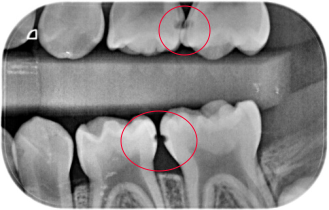

小心邻面龋,一坏坏俩

图片尺寸791x400